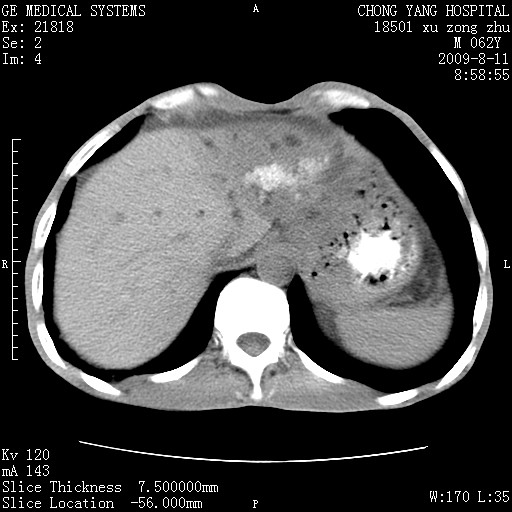

以下是引用杀毒软件在2009-8-11 16:35:00的发言:[br]肝内胆管扩张局限于左叶,胆管内有结石伴肝外胆管结石,胆管壁增厚呈弥漫性并发腹腔积液,胰腺边界模糊。[br][br]考虑---胆总管及肝内胆管结石继发胆管炎及胰腺炎,左肾下极囊肿,腹水。

以下是引用zjzjr在2009-8-11 17:35:00的发言:[br]肝内胆管扩张局限于左叶,胆管内有结石伴肝外胆管结石,胆管壁增厚呈弥漫性并发腹腔积液。[br][br]考虑---胆总管及肝内胆管结石继发胆管炎,左肾下极囊肿,腹水。